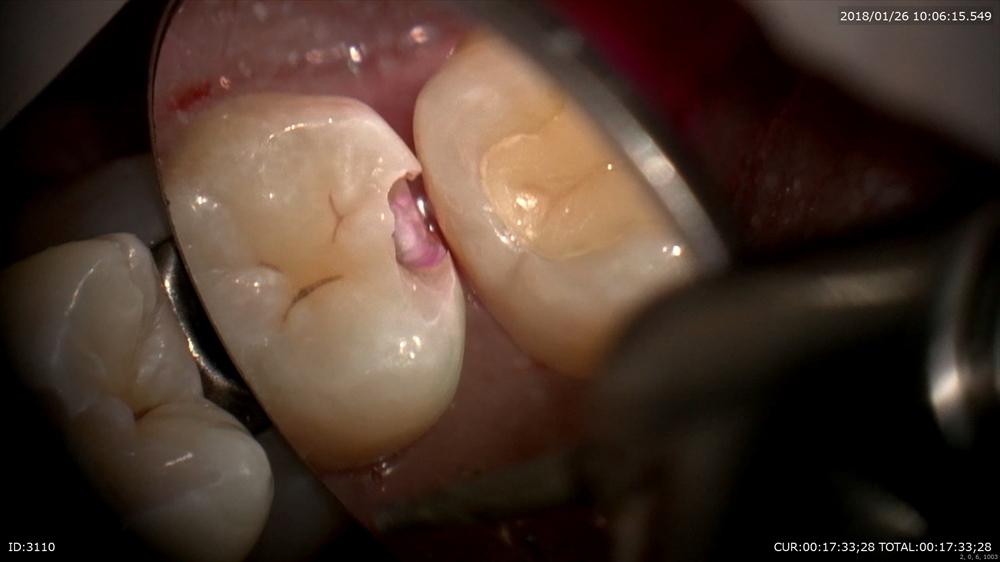

次の方。一見ちょっと黒いけど。。。。歯科ドックで発覚しました。この下にむし歯があります。

ギャー!!!ドックやってよかった。

神経に近い所はMTAセメントで

二層目

マイクロスコープで直視できます。ピコモラー最高!!